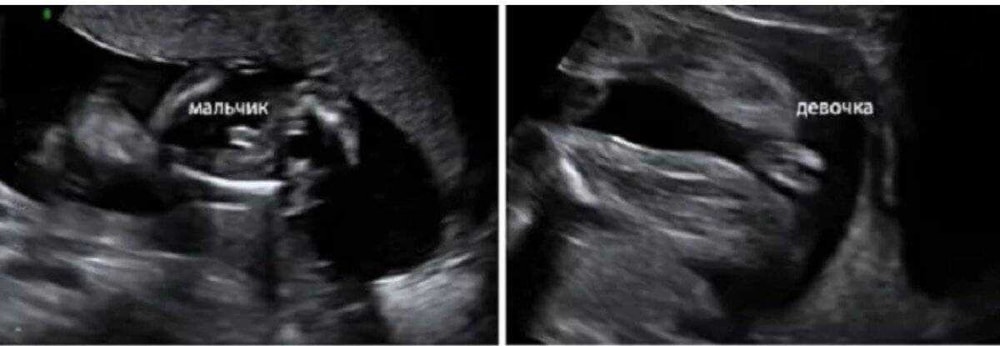

По моему, мошонка это. А пенис наверх смотрит, наверное. Но это я так вижу.

Вот вид снизу у девочки, срок 15 недель.

Жужу, да ну, явно же видно "кофейное зернышко". А вот на вашем снимке вижу прям мошонку)

Просто это может быть мошонка, а пенис вверх смотреть. У моей прям хорошо видно было, что половые губы и клитор,но и узи было в 20 нед., а тут я сразу подумала - мошонка...

Жужу, всмысле?) на втором же, две ноги бедренная кость, вид снизу - _- или что вы не можете понять?))